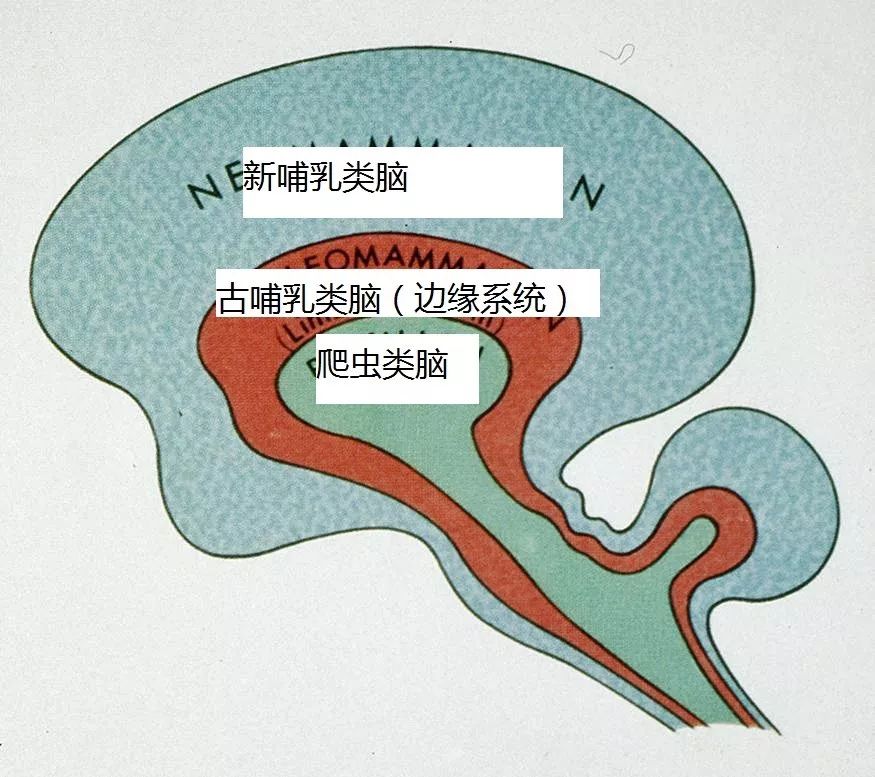

神经科学家Paul MacLean做了一个简单的图,来阐述我们前面提到的爬虫类脑最早出现——然后是哺乳动物对脑进行了完善——最后又进行了完善后成为了我们现在的大脑三元件的理论。

这就是我们的脑的大概分布:

我们分部分来看 :

爬虫类脑:脑干和小脑

这是我们大脑里最古老的一部分

就是图中青蛙大佬所占据的那部分。事实上,一个真的青蛙的脑和人类脑的这一部分是非常相似的,下图是青蛙脑的照片。

当你理解这部分脑的功能后,这部分脑的“古老”就显而易见了——这部分脑能做到的功能,青蛙和蜥蜴也能做到。

古哺乳动物脑: 边缘系统

新哺乳动物脑: 皮质(Cortex)